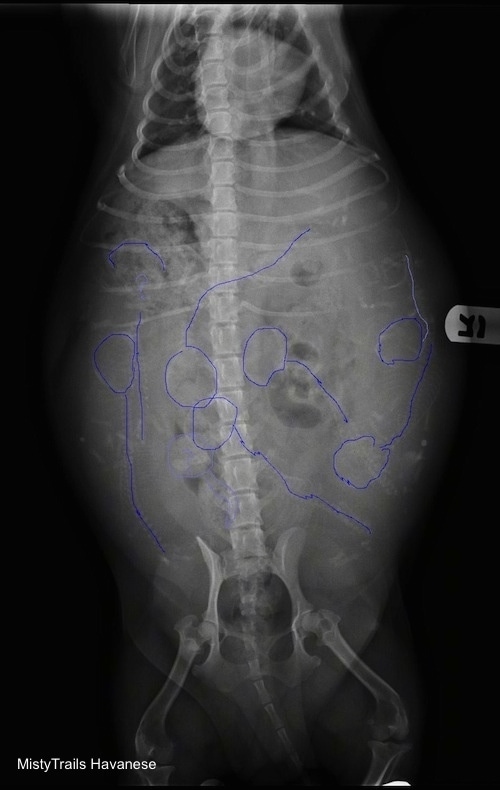

У беременных сук увеличение матки можно зафиксировать только на 21-й день беременности. С 21-го но 42-й день беременности можно видеть увеличенные, наполненные жидкостью рога матки. Скелеты плодов становятся рентгенонепрозрачными на 44-47-й день беременности или на 35 40-й день диэструса, а череп и позвоночник становятся видны раньше длинных костей и костей пальцев. Для постановки точного диагноза беременности нужно 2 дня (Сопсаппоп andRendano, 1983). Зубы плодов различают на 58 63-й день. Если основываться на дате первой вязки, то минерализацию скелета можно идентифицировать уже на 42-52-й день после вязки После 47-го дня беременности, когда скелеты плодов будут минерализованы настолько, чтобы стать рентгенонепрозрачными, но рентгеновским снимкам можно определить размер помета. Он зависит от многих факторов, но чаще всего у мелких пород в — будет 2- 4 щенка, у средних пород — 4 7, а у крупных собак от 6 до 10 щенков. Рентгенография позволяет точно подсчитать численность малого помета, но даже несмотря на се более высокую точность но сравнению с ультрасонографией, на рентгеновских снимках нс всегда возможно подсчитать количество щенков в больших пометах. Самый легкий путь определения размера помета — подсчет количества черепов и позвоночников на рентгеновских снимках (рис. 8 и 9).

Щенки щенков

Ниже приведены различные рентгенограммы беременных дам, которые вот-вот родятся. Некоторые из них обозначены позициями щенков, чтобы помочь вам лучше понять, как определять щенков.

Этот рентген показывает пример того, почему важно делать рентгенограммы беременной дамбы. У этой дамбы только два щенка, и в результате щенки стали очень большими из-за всей дополнительной комнаты.Этой дамбе понадобится кесарево сечение, чтобы вытащить щенков. Как только у нее понизится температура, ветеринар выполнит процедуру, чтобы обеспечить безопасность как щенков, так и плотины.

Если вы сделаете рентген в дни 55/56/57, то сможете увидеть головы, позвоночники, ребра и ноги.Сначала посчитайте головы, а затем найдите позвоночник, который будет идти с каждой головой. На этом рентгеновском снимке точно показаны шесть щенков одинакового размера, и ничего страшного. Там может быть семь щенков, с возможностью восьми. Смотрите рисунок ниже, чтобы помочь найти щенков

На этой картинке изображены щенки, которых можно увидеть наверняка.